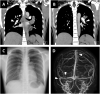

A 22-year-old woman was admitted to the hospital with complaints of headache and vomiting. Radiological examinations revealed cerebral sinus venous thromboses, pulmonary thromboembolism, and cavities in the left upper lung. Pulmonary tuberculosis was diagnosed based on sputum and gastric aspirate culture. Heparin followed by warfarin was administered. Anti-tuberculosis agents including rifampicin were also initiated. Since the effect of warfarin did not reach the therapeutic level because of interaction with rifampicin, edoxaban was administered and thromboses were ameliorated. This report illustrates rare thrombotic complications in a TB-induced hypercoagulable state and the potential benefits and safety of edoxaban in combination with rifampicin.